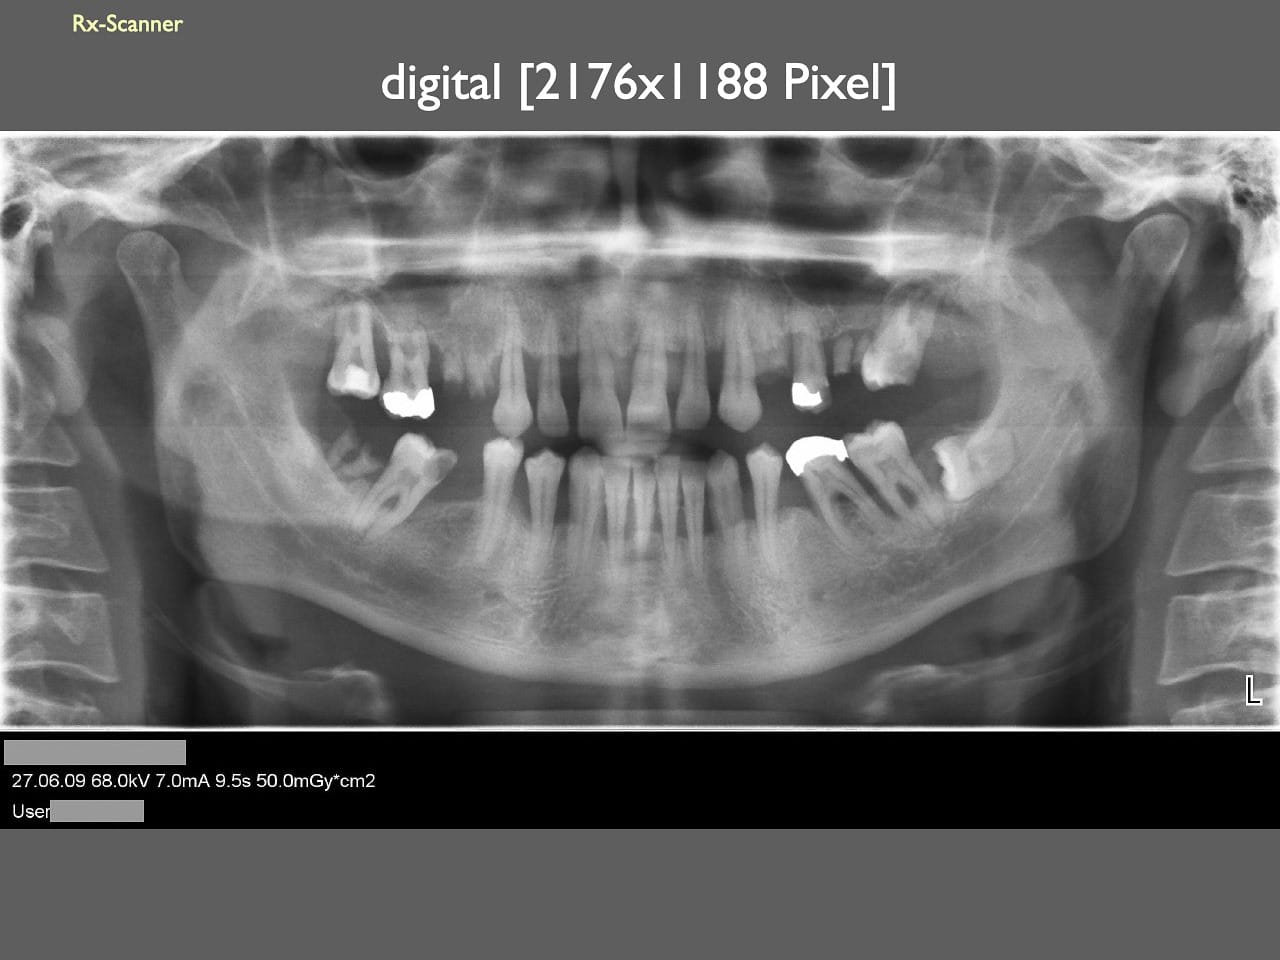

dental Scannen in der Zahnarztpraxis. Study Club vom 28.2.2010. Von peter portmann, Veröffentlicht am 28. Feb. 2010 — 3 min Lesezeit dokumentationfoto Auf dieser Seite Zahnarztpraxis-Trilogie zu Fotografie und Dokumentation Portrait Fotografie Scannen Scannen